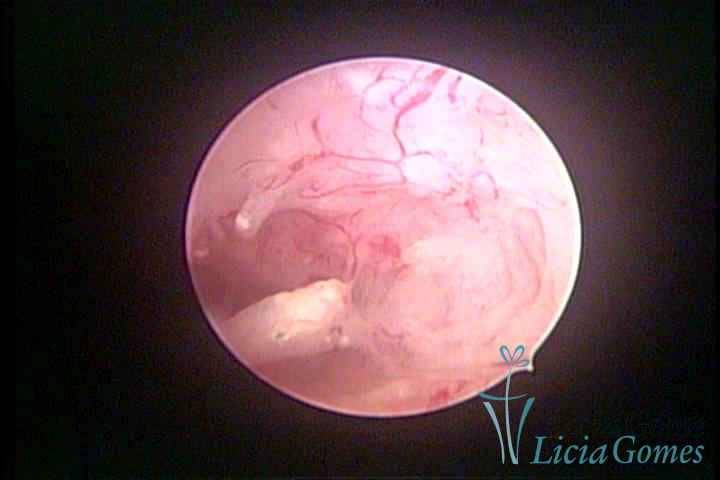

Este pode apresentar uma gama variável de aspectos macroscópicos, com aspecto pseudopolipoide; lembrando tecido cerebroide ou com reação deciduoide;a vascularização superficial é mais evidente e com vasos em formatos de saca-rolha ou espirais visualizando também a vascularização com atípias, com aumento do calibre dos vasos superficiais, pode ser encontrado também tecido em necrose, poderá haver um pequenos dendritos (papilomatoso).